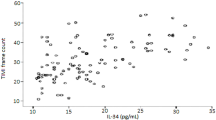

The PIV of patients in the CSFP group was observed to be higher compared to the NCF group (p < 0.001) (Fig. 1). Spearman Rho Correlation Coefficient analysis revealed a significant positive correlation between PIV and mean TFC (r = 0.518, p < 0.001) (Fig. 2).